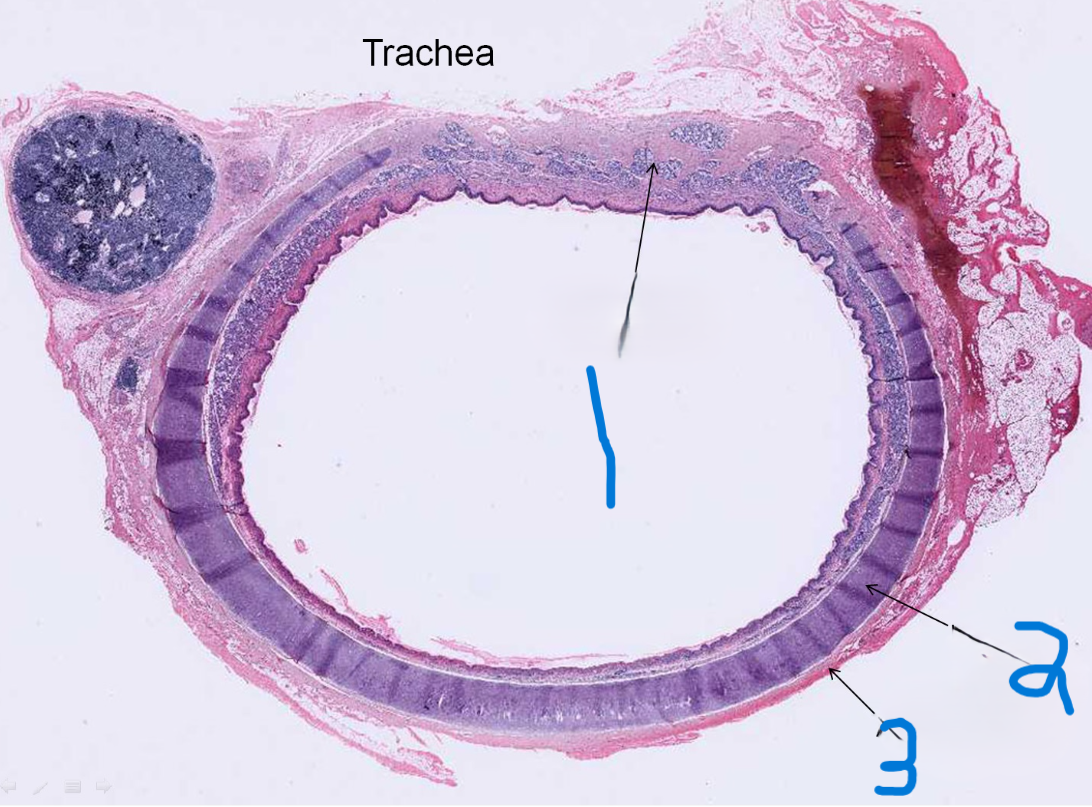

What is depicted by #1

Hyaline cartilage

What is depicted by #2

Adventitia

What is depicted by #3